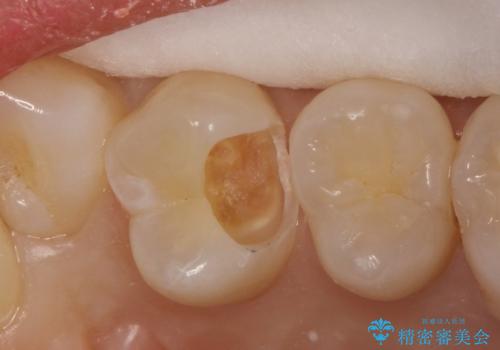

インプラントや義歯を用いることなく咬合を回復することができ、喜んで頂けました。

治療期間も抜歯後3ヶ月以内かつ少ない来院回数(初診含めて6回)で治療を終えることができ、ご満足頂けました。

被せ物の種類:メタルボンドクラウン エコノミー フルベイク